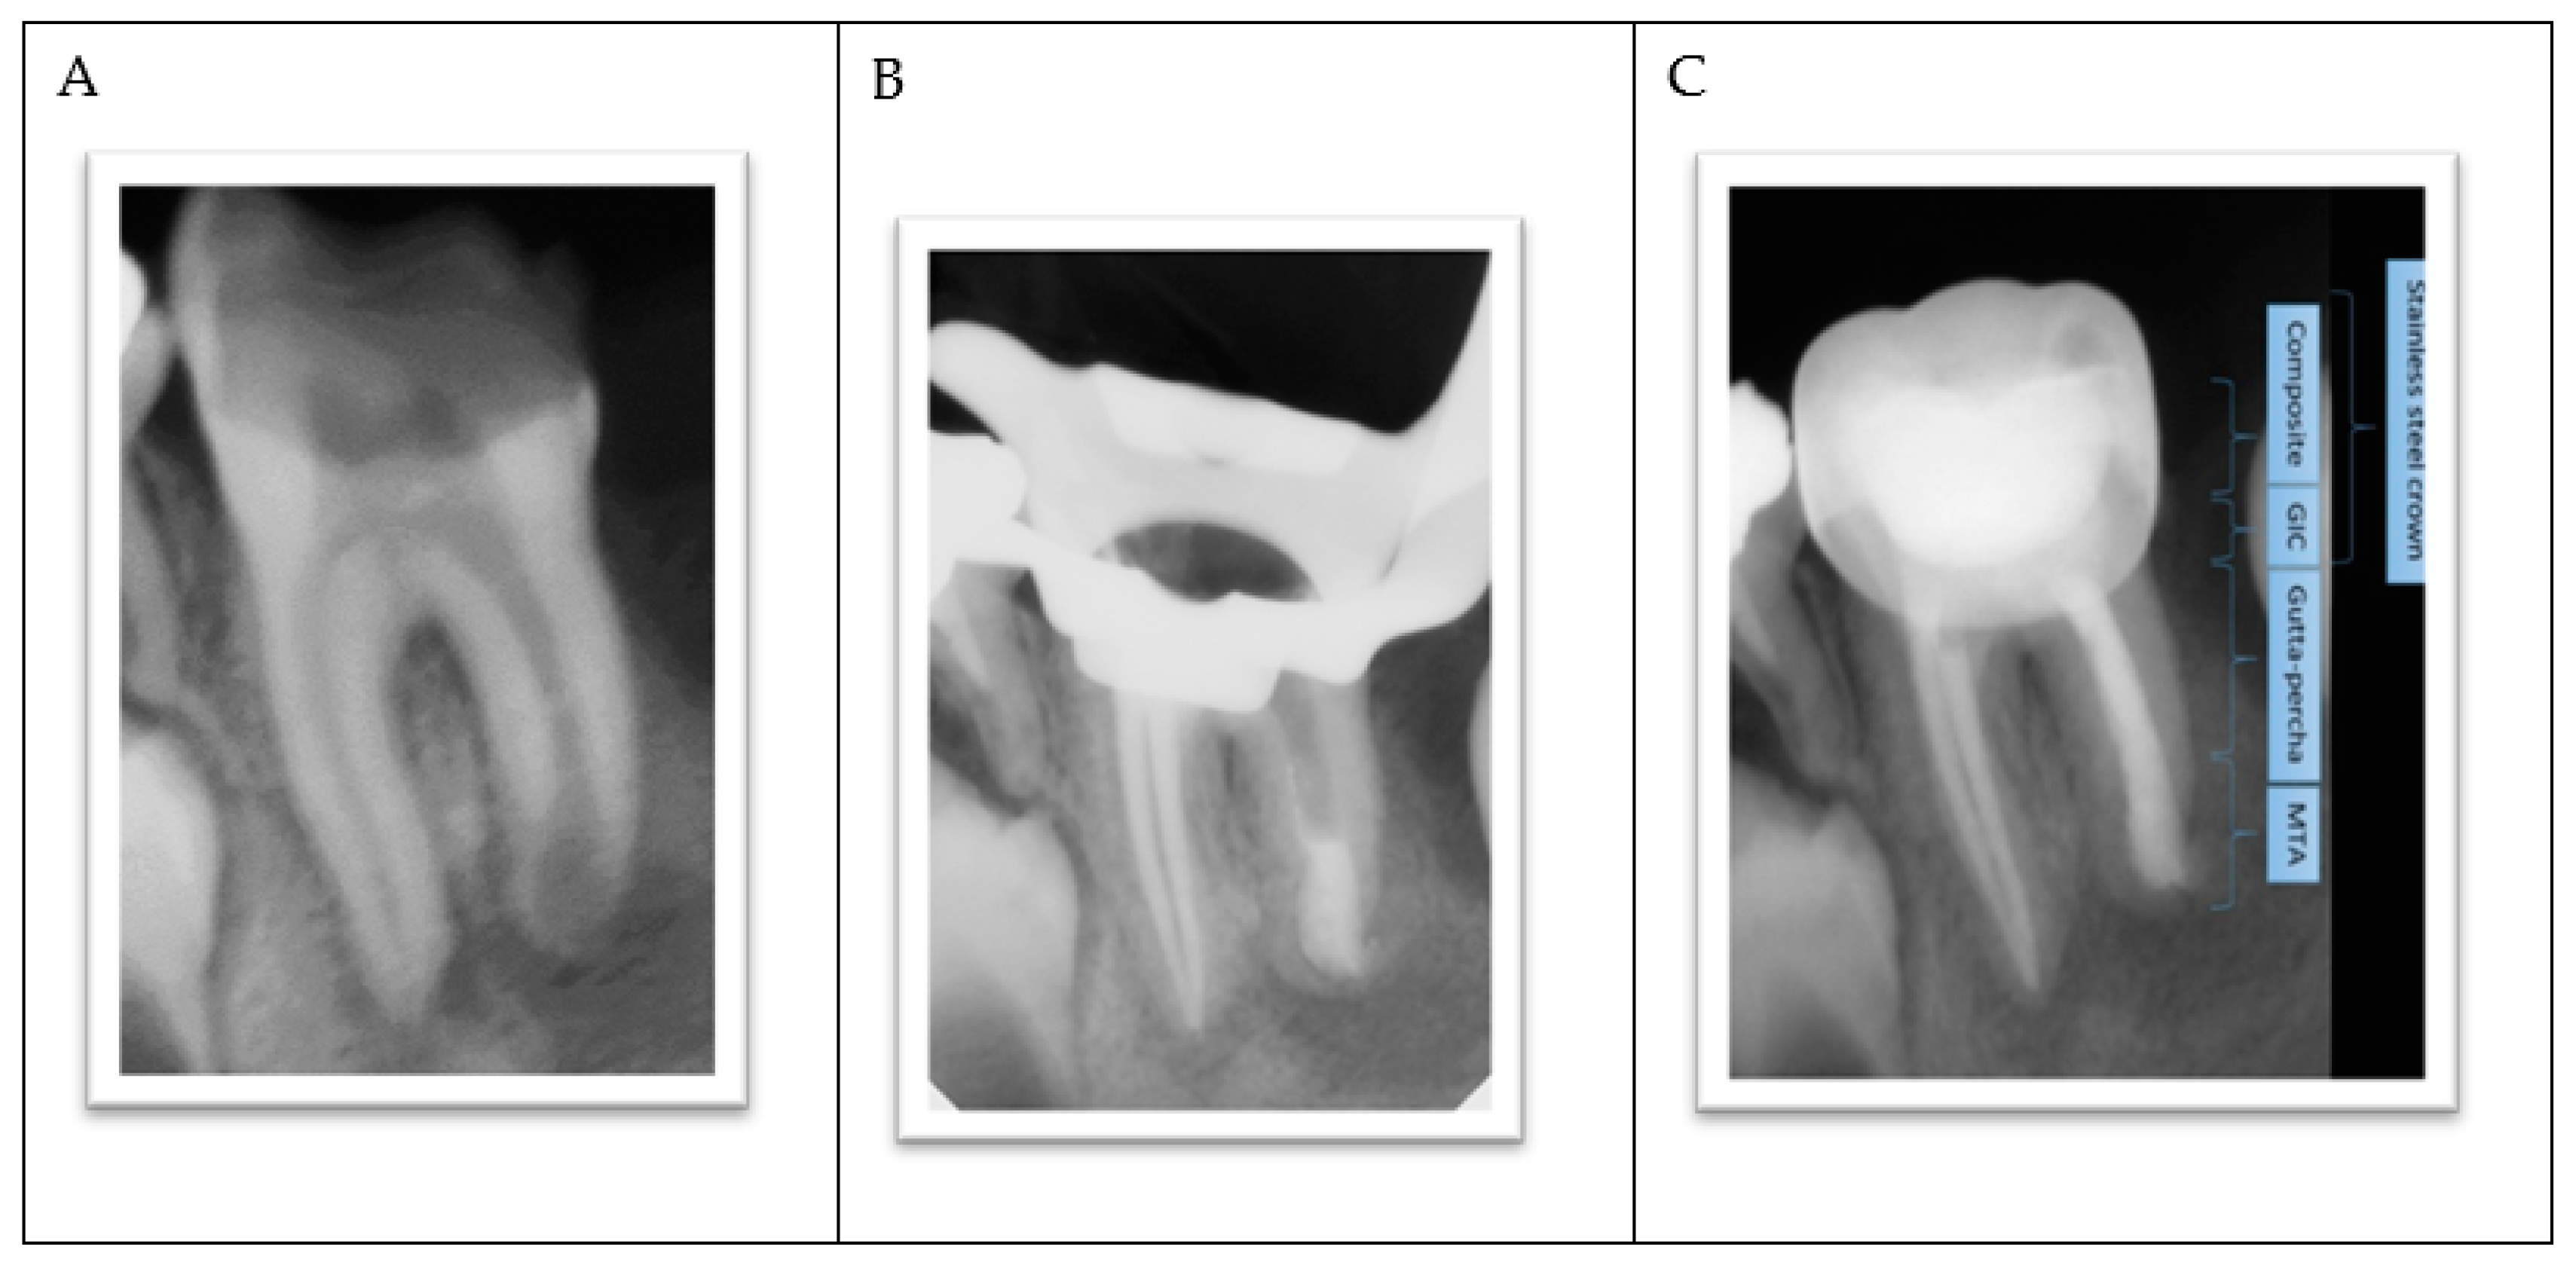

The lower-left permanent molar (tooth #36) had necrotic pulp and apical lesions. The tooth’s distal root had an open apex, whereas the mesial root showed a closed apex. It was decided to do a traditional root canal in the mesial canals and insert an apical plug using mineral trioxide aggregate (MTA) in the distal root (Figure 4A–C).

Figure 4.

(A) Apical lesions with extensive decay in tooth #36. (B) Verifying the placement of the MTA plug. (C) Completed root canal treatment and placement of a metallic crown.

- The procedure involved local anesthesia, a rubber dam, and removal of caries.

- Working length was established using a radiograph.

- Copious irrigation with 2.5% sodium hypochlorite NaOCl, followed by minimal mechanical instrumentation of the root canal walls and additional irrigation with Q-mix (Dentsply Sirona) and ultrasonic activation was performed.

- Mesial canals were obturated with gutta-percha using a lateral condensation technique while the distal root was treated with MTA as an apical plug because there was no apical stop.

- A moist cotton pellet was placed in the canal to facilitate MTA setting, and the access cavity was restored using a glass ionomer cement.

- The next day, the setting of the MTA plug was verified, and the remaining portion of the root canal was filled with gutta-percha using lateral condensation. The pulp chamber was cleaned and the coronal access double-sealed with a bonded resin composite.

- A stainless steel crown was inserted.